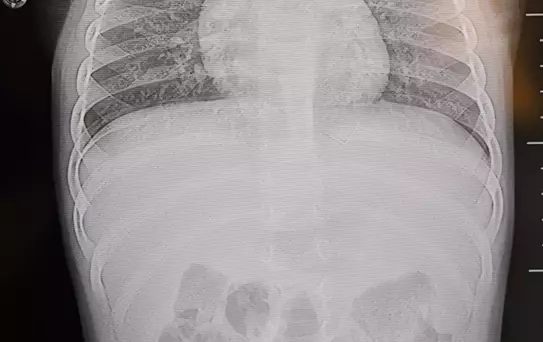

Kahramanmaraş'ta sırt üstü yatmak istemeyen ve yatırıldığında ağlayan ve huzursuzluk çıkaran 1 yaşındaki bebeğin sırtından akciğer zarına doğru ilerleyen 2 santimetrelik zımba teli çıkarıldı. Vakayla ilgili konuşan Prof. Dr. İdris Altun, "Cisim alınmasaydı enfeksiyon gelişebilir omurilik kanalında ciddi hasarlar oluşabilirdi" dedi.